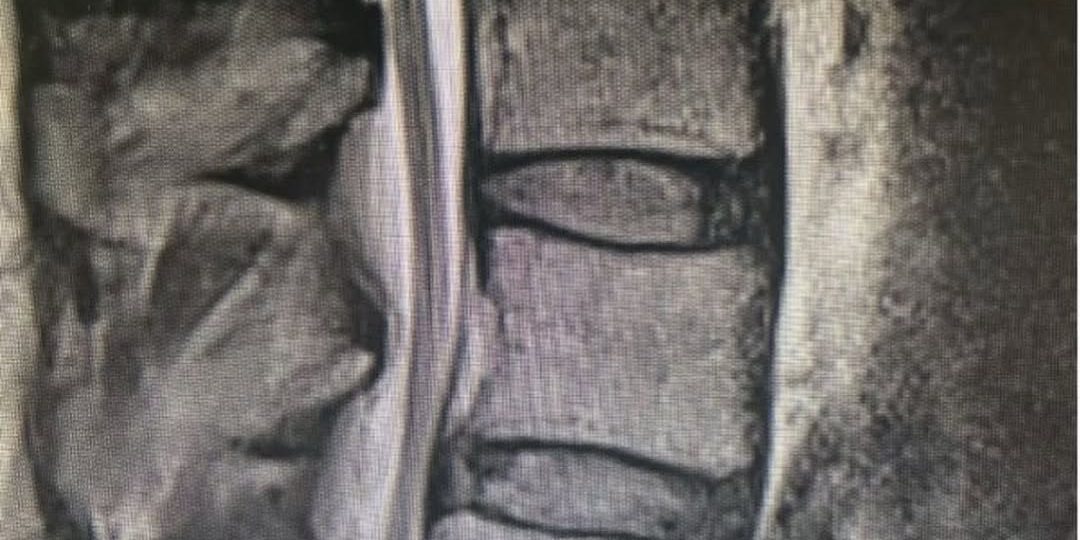

The third image is the postoperative X-ray taken six weeks after the L4 and L5 laminectomy and Transforaminal Lumbar Interbody Fusion (TLIF) back surgery.

In doing the TLIF spinal fusion, the surgeon stabilized the spinal vertebra. The result? It resolved all of the patient’s symptoms including his back pain and leg pain.